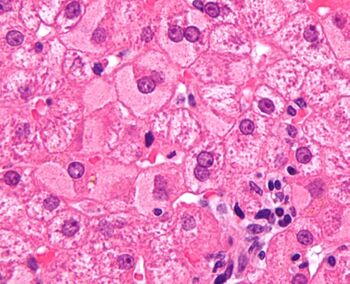

In liver pathology, a ground glass hepatocyte, abbreviated GGH, is a liver parenchymal cell with a flat hazy and uniformly dull appearing cytoplasm on light microscopy. The cytoplasm's granular homogeneous eosinophilic staining is caused by the presence of HBsAg.

The appearance is classically associated with abundant hepatitis B antigen in the endoplasmic reticulum, but may also be drug-induced.[1][2] In the context of hepatitis B, GGHs are only seen in chronic infections, i.e. they are not seen in acute hepatitis B.

Micrograph showing ground glass hepatocytes. H&E stain.